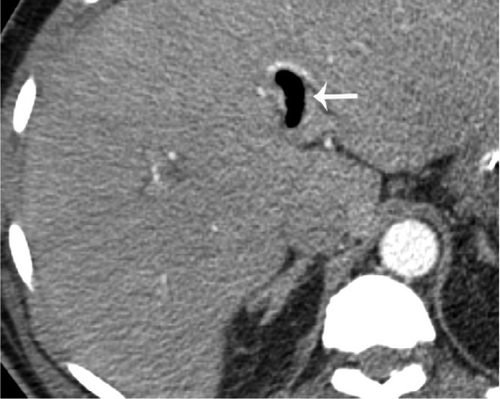

Сотрудники отделения радиологии Массачусетской общей больницы в Бостоне (США) обнаружили у некоторых зараженных коронавирусом пациентов аномальные изменения в желудочно-кишечном тракте. Чаще всего они выявлялись у тяжелых больных. Об этом говорится в исследовании, опубликованном в журнале Radiology, пишет "Российская газета".

Ученые проанализировали данные 414 пациентов, которые поступили на лечение с 27 марта по 10 апреля 2020 года. Их средний возраст составил 57 лет, многих из них подключили к аппаратам ИВЛ. Нарушения со стороны кишечника наблюдались у 31 процента заболевших.

"Мы обнаружили аномалии в работе кишечника у пациентов с COVID-19. Они чаще фиксировались у лежащих в отделении интенсивной терапии. Чтобы понять причину таких изменений, необходима дополнительная работа", - заявил доктор медицинских наук Раджеш Баяна.

В частности, как пояснил специалист, у некоторых пациентов с COVID-19 внезапно развивался пневматоз - патологическое состояние системы пищеварения, при котором газы проникают в толщу стенки кишечника и образуют там воздушные кисты. Кроме того, у нескольких людей было выявлено необычное желтое обесцвечивание кишечника, еще у трех больных - инфаркт кишечника.